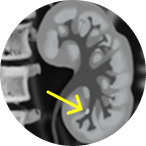

Jelmyto® (mitomycin) for pyelocalyceal solution is indicated for the treatment of adult patients with low-grade Upper Tract Urothelial Cancer (LG-UTUC).

This portrays real-world scenarios in which JELMYTO was used in a diverse range of tumor types. UroGen's Olympus trial studied patients with treatment-naïve or recurrent LG-UTUC with ≥1 measurable papillary tumor 5 to ≤15 mm located above the ureteropelvic junction (tumor debulking was permitted prior to study enrollment for tumors >15 mm).1 For additional inclusion and exclusion criteria, please see the Olympus trial study design.